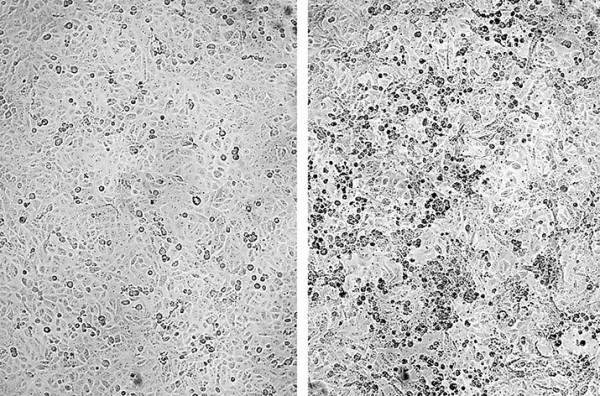

Рисунок 1. Микрофотографии клеток Vero E6: слева — контрольные клетки, справа — клетки, инфицированные B.1.1.529.

«Мы провели анализ нейтрализующих антител в образцах сыворотки людей, вакцинированных рекомбинантной вакциной на основе аденовируса «Спутник V» (rAd26-S + rAd5-S) и ревакцинированных вакциной «Спутник Лайт» (rAd26-S). Мы выделили жизнеспособный вариант вируса SARS-CoV-2 «омикрон» (B.1.1.529) от пациента, прибывшего из Южной Африки (см. рис. 1) и после проведения секвенирования использовали его для анализа вируснейтрализующей активности сывороток вакцинированных и ревакцинированных лиц. Исследование проводилось с сыворотками людей, вакцинированных «Спутником V» 6–12 месяцев назад, а также с сыворотками людей, которые были повторно вакцинированы «Спутником Лайт» 2–3 месяца назад. RBD-специфический IgG был обнаружен во всех проанализированных образцах сыворотки (см. рис. 2).